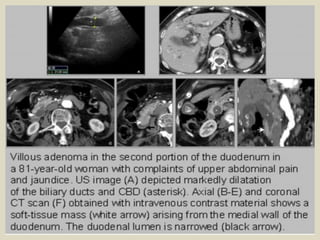

Choledocholithiasis A 35 years old female presented with jaundice. (a) US imaging

shows a dilated CBD obstructed by a stone with a posterior acoustic shadow. (b) CT

(coronal oblique reconstruction without injection) shows the dilatation of the CBD